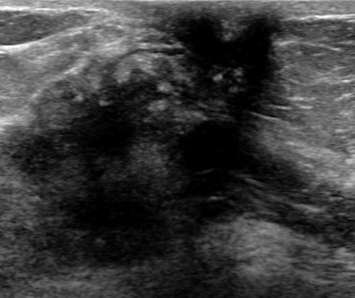

Retraction: Any focal invagination of the skin (often noted as nipple inversion or skin dimpling on physical exam) should be noted, because, like with architectural distortion, this may suggest deeper pathology. Below is an ultrasound demonstrating nipple retraction with an underlying heterogeneous mass with irregular contours. This lesion was highly suspicious (BIRADS 5) and proven to be invasive ductal carcinoma on biopsy.

Ultrasound demonstrating nipple retraction with an underlying heterogeneous mass with irregular contours.